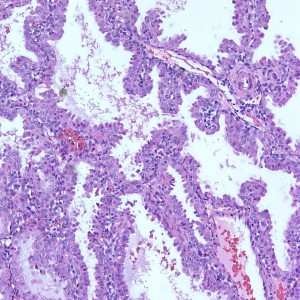

As we can see, enlarged and hydropic chorionic villi are not especially difficult to find (circle). None of these villi however demonstrate trophoblastic inclusions. There are rare interspersed small chorionic villi (top left) however they are generally rare.

Some villi are so large and hydropic that a few have actually developed central cisterns, spaces within the center of the villi (space highlighted by horizontal lines).

This large hydropic villus with central cistern also demonstrates an important finding: the loss of polarity of the surrounding trophoblasts with circumferential proliferation of variably atypical trophoblastic cells (arrows).